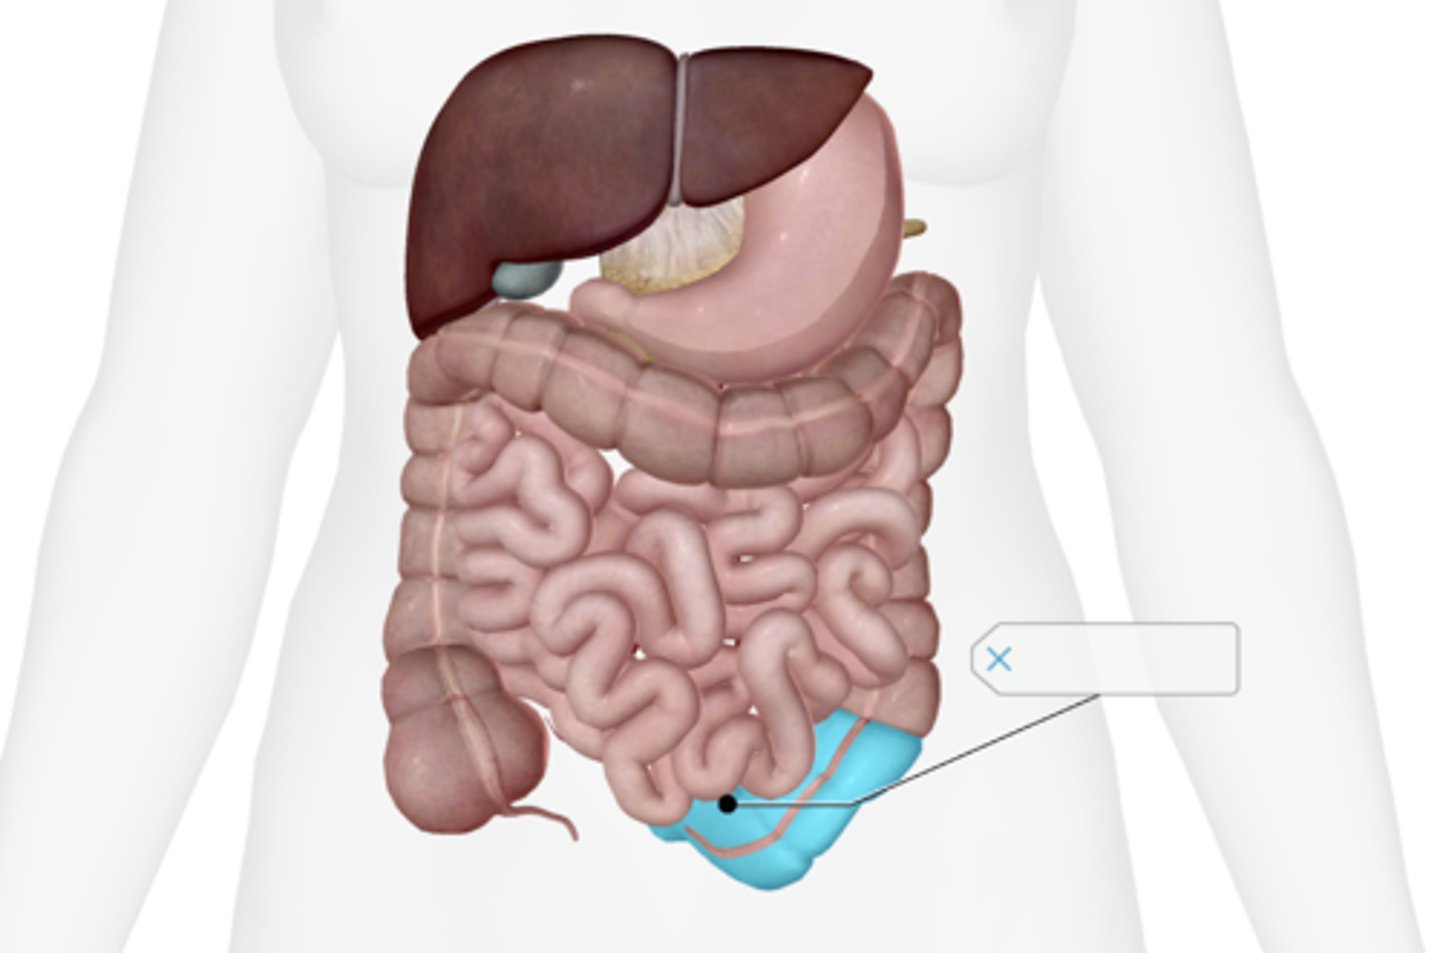

Cecum

Appendix

Ascending colon

Transverse colon

Descending colon

Sigmoid colon

Rectum

Anal canal